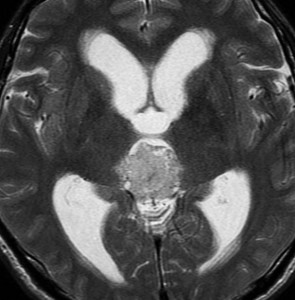

成人男性の松果体芽腫です。左のCTでは白く見える石灰化があります。水頭症があって頭痛と嘔吐で発症しました。右のMRIでは腫瘍の形が丸くなくて周囲の脳に浸潤したり脳室の壁などにべっとり広がっているように見えます。悪性腫瘍の特徴的な像で,開頭手術をしても摘出できないことが判ります。松果体芽腫は悪性度が高くて(WHOグレード4),脊髄などに播種転移したりしますし,手術だけでは治りません。

腫瘍は定位脳手術で生検をしました。水頭症に対しては内視鏡で第3脳室開窓術を行なって症状を改善しました。左のMRIで水頭症が良くなっているのが判ると思います。それから,全脳脊髄に30グレイの放射線治療をして腫瘍局所には24グレイの照射を追加しました。同時にICE化学療法というのを6コースしました。右のMRIでは治療が終わって小さく固まった残存腫瘍が見えます。この残存腫瘍は第3脳室の壁にくっついていて摘出するリスクがとても高いと思いましたので,そのままずーっと10年間様子を見ていますが再発していません。でも,残存腫瘍がなんとか取れる時は徹底的に取ってしまった方が再発率は少ないといえます。